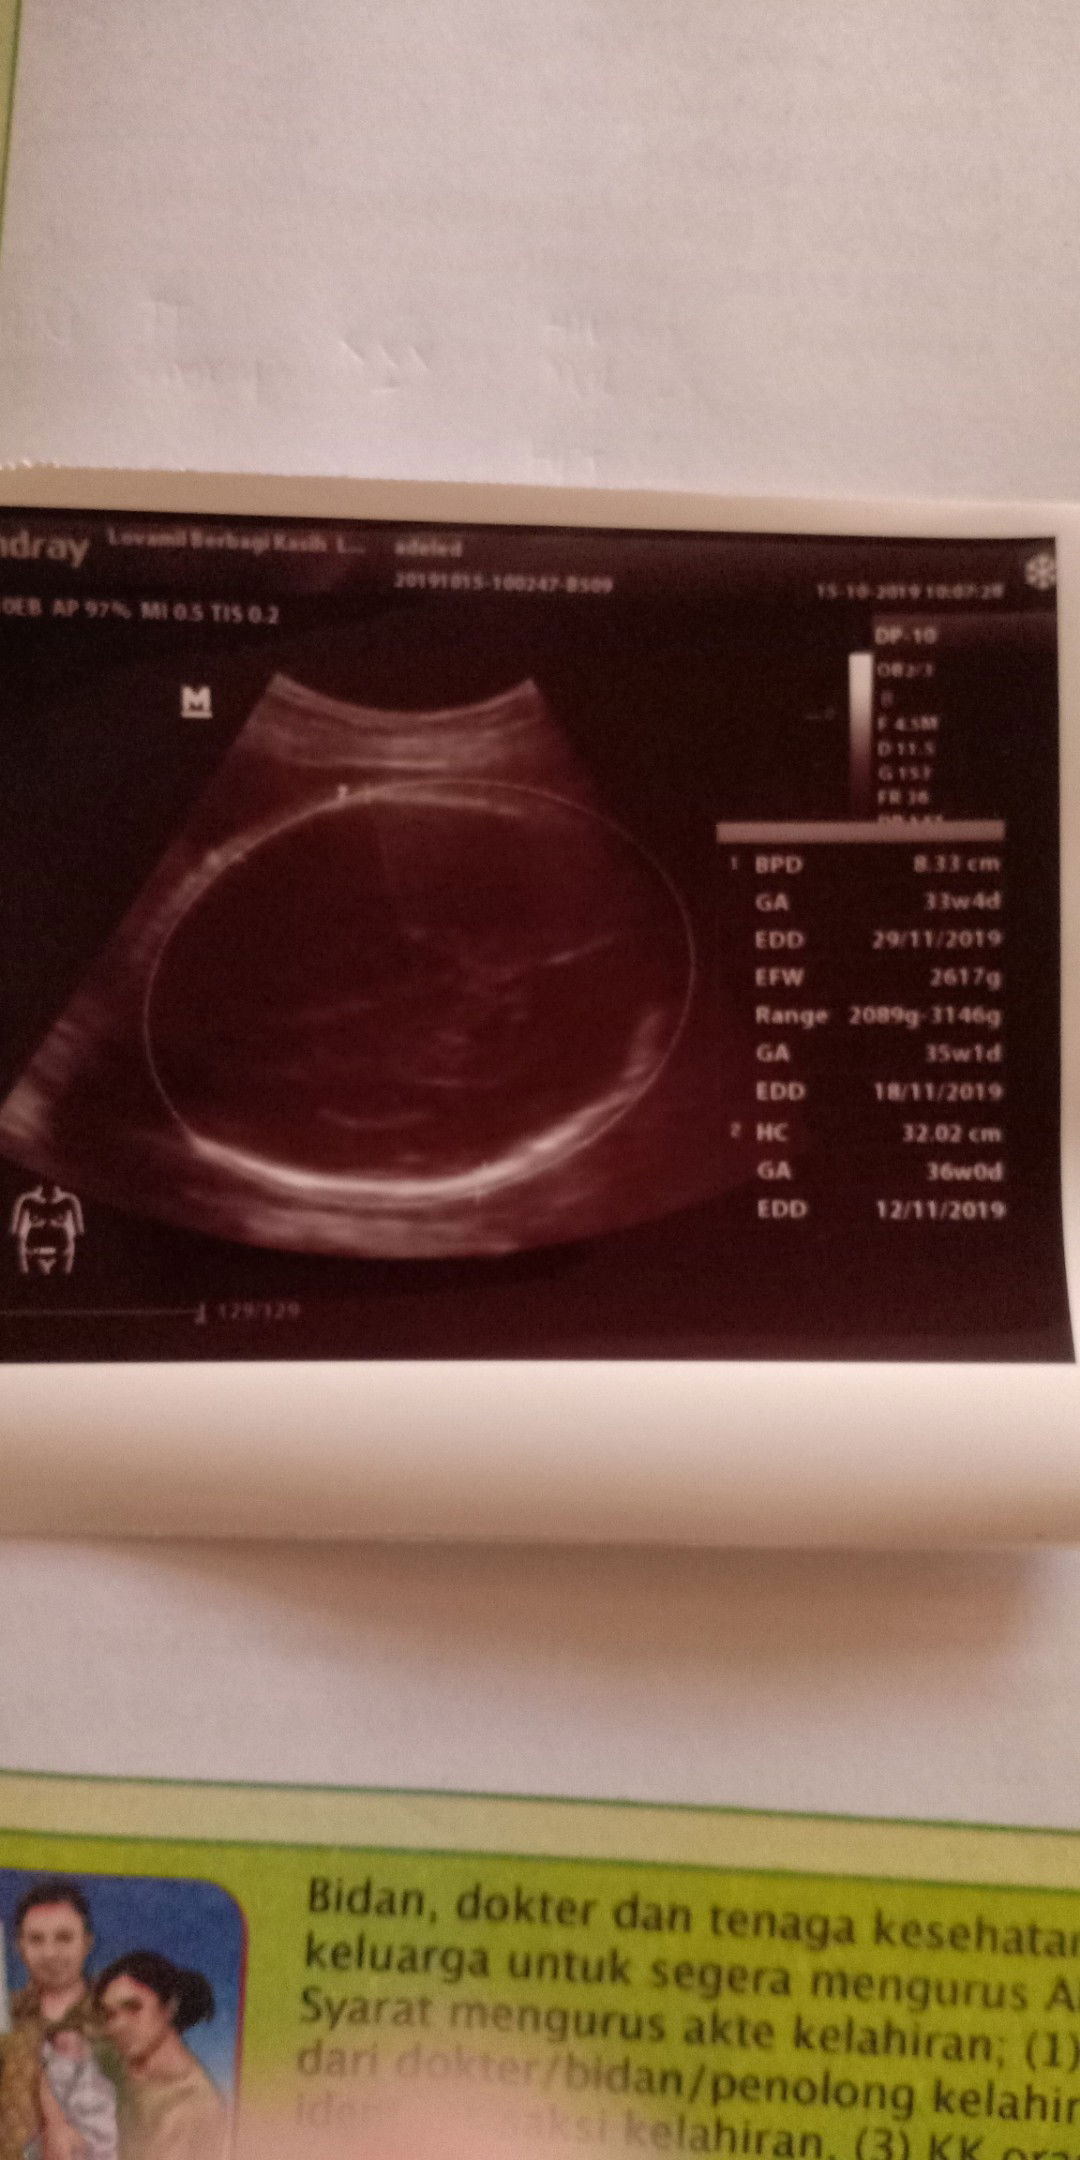

hasil usg

Bun ini hasil usg aku.. Masih normal kan bun ? Soalnya gk sempat tanya banyak ke dokter.

Ini hasil usg aku. Tapi tadi gk sempat tanya banyak ke dokter. Jadi masih agak bingung. Mohon bantuan penjelasannya ya Bund ?

BPD

Bun BPD normal untuk bayi 33 minggu berapa ya ?